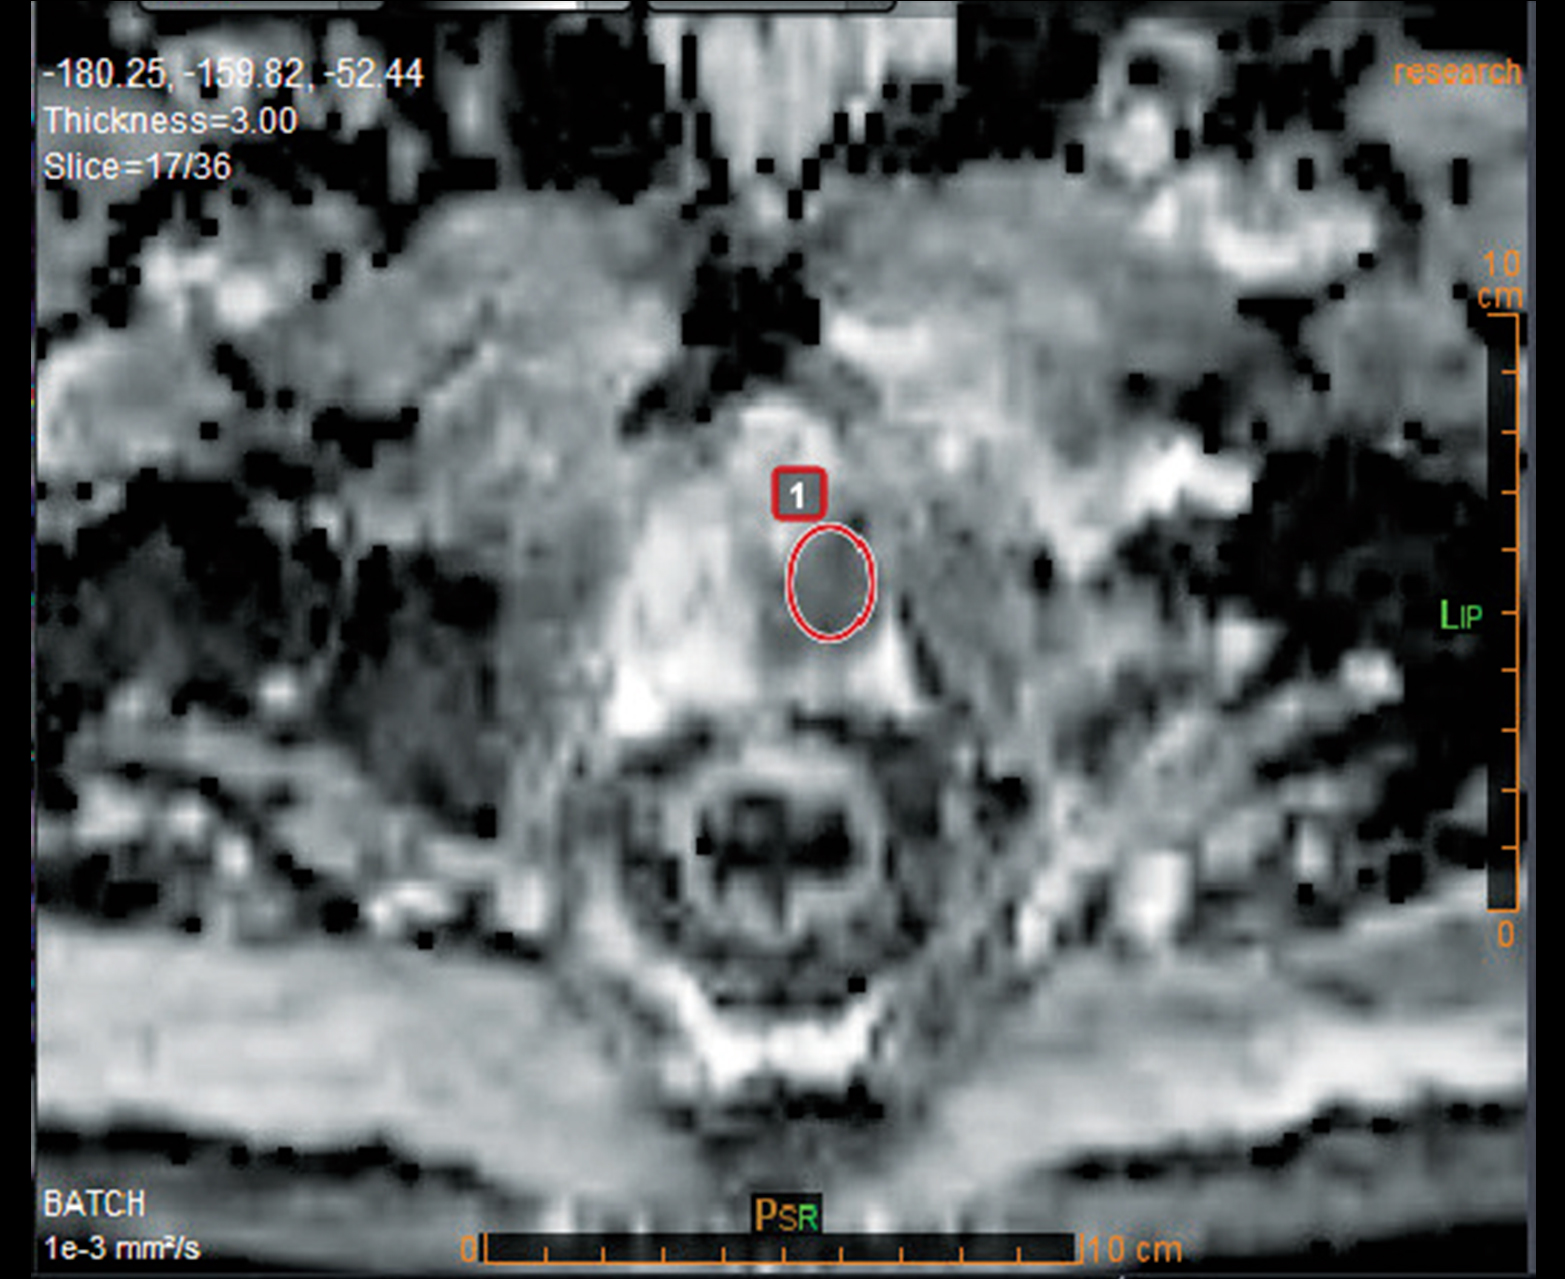

Многопараметрическое настраиваемое отображение карт диффузии и перфузии, включая карты rCBV_corrected и K2

Количественные карты проницаемости головы и шеи

Расчет АЦП и других качественных и количественных карт